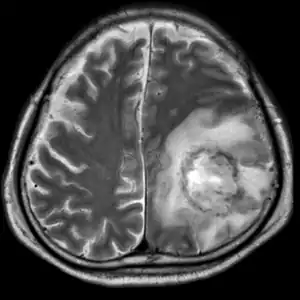

| T2-weighted MRI showing liquefied, necrotic brain tissue as a result of GAE caused by an infection of Acanthamoeba, genotype T18 | |

A: T2-weighted MRI showing liquefied, necrotic brain tissue as a result of GAE caused by Balamuthia mandrillaris

B: T1-weighted MRI showing expansion and addition of necrotic areas 4 days later